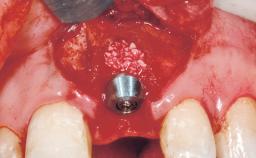

A 30-year-old female patient had lost tooth 21 and was referred to our clinic for consultation and treatment. Due to advanced apical infection, tooth 21 had been extracted two months earlier at another clinic and an acrylic-resin tooth had been bonded to the adjacent teeth. The patient desired implant treatment to avoid any damage to the adjacent natural teeth. While the patient had no history of any systemic disorder, she was a heavy smoker and exhibited medium to advanced periodontitis in the entire jaw. After the initial treatment to achieve a pocket probing depth of less than 4 mm and no bleeding on probing, a decrease in the height of the papillae mesial and distal to the extraction site and overall gingival recession were observed.

| Bone Augmentation | Horizontal|Staged |

| Augmentation Materials | Autogenous chips|Membrane |